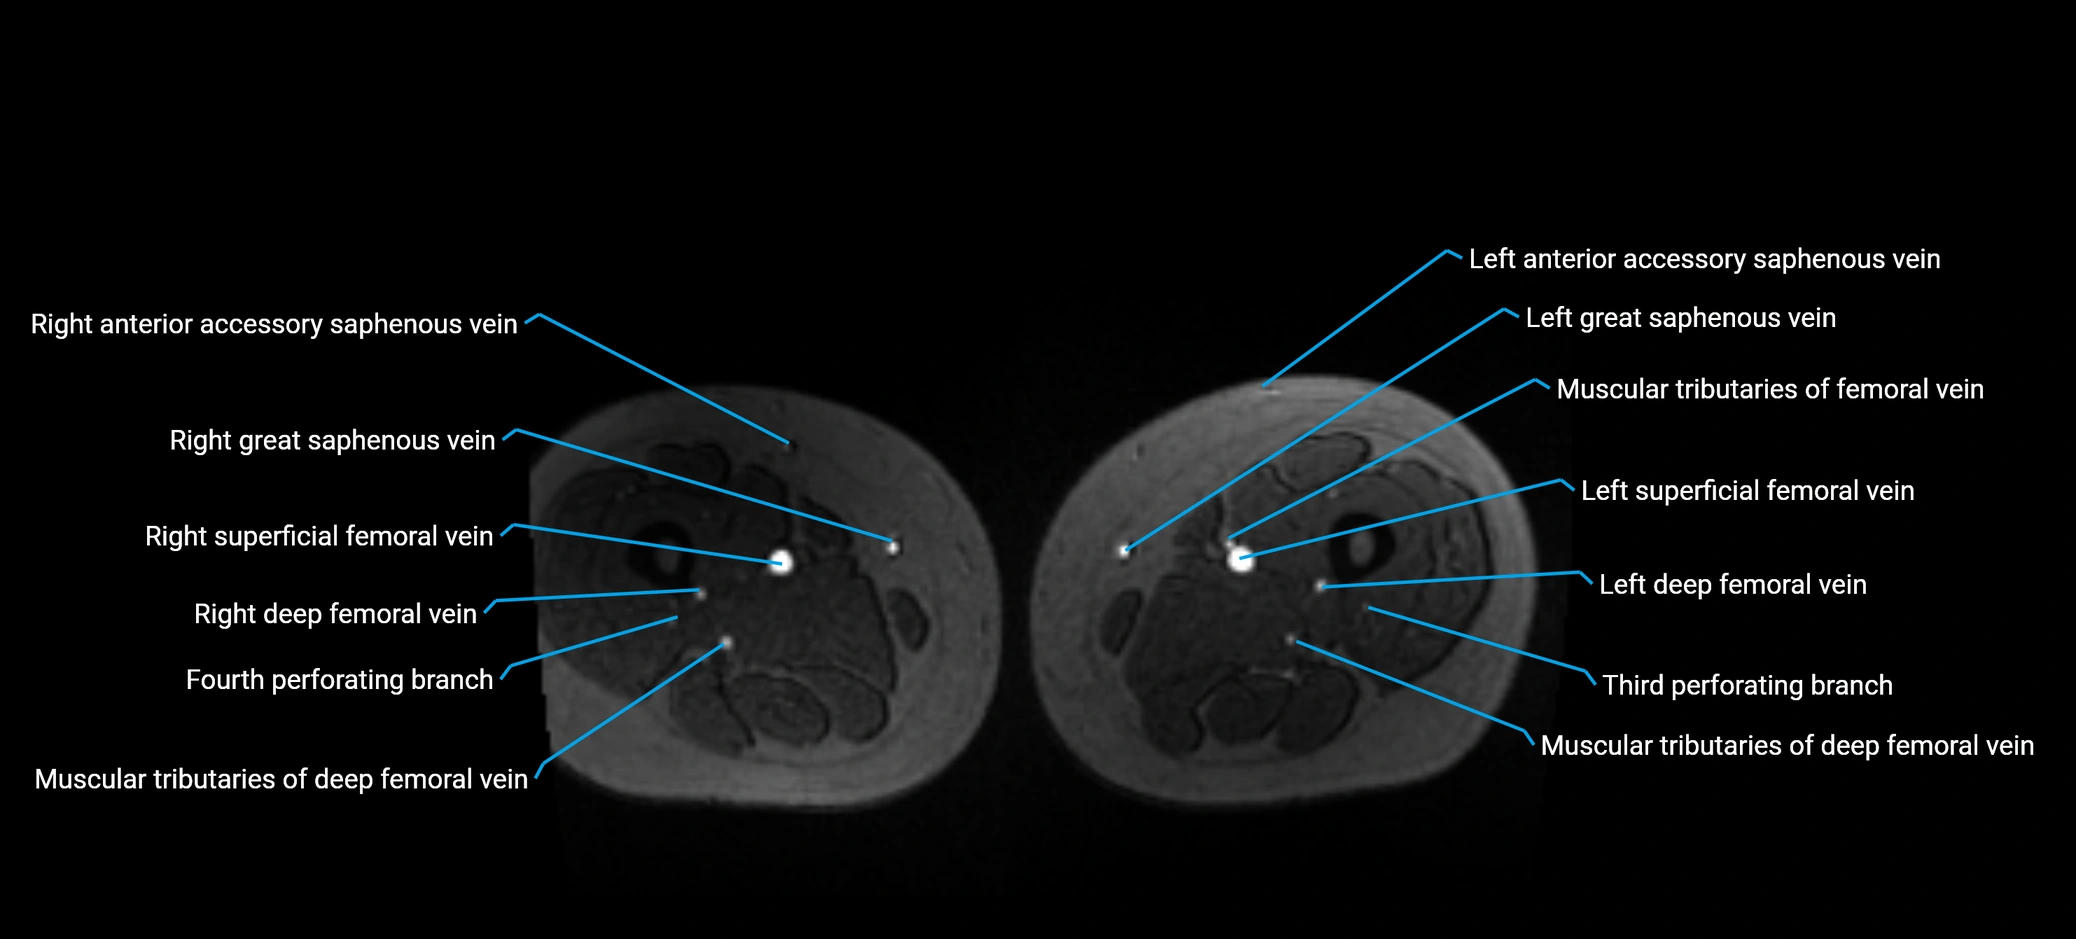

MRI image

image